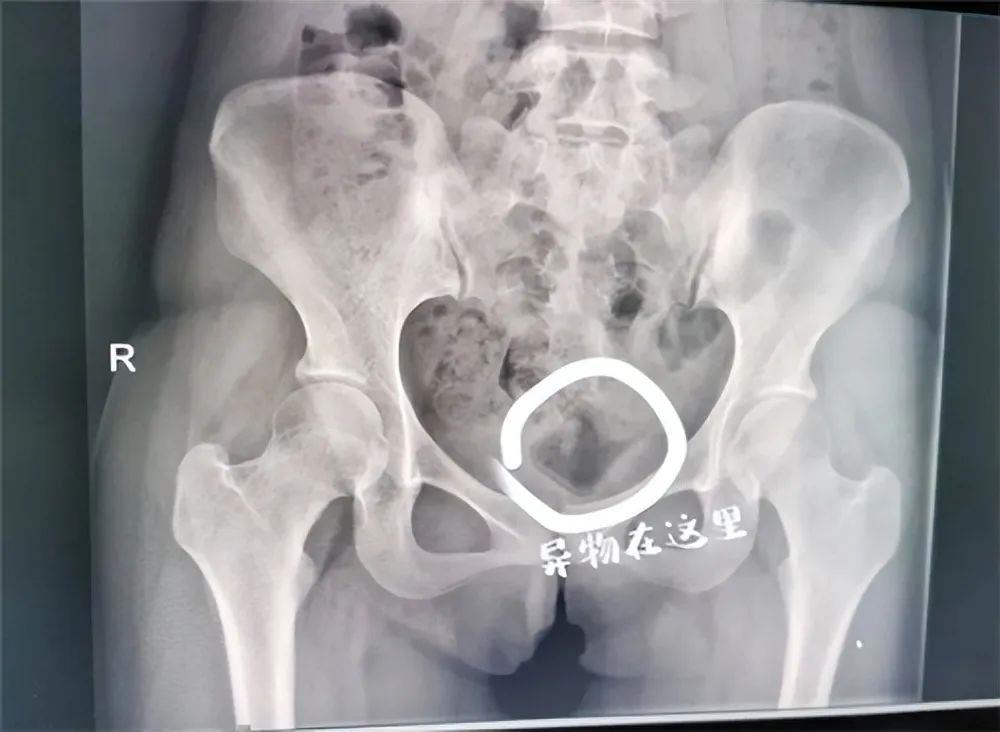

结果就是拿不出来。小杨傻眼了。之后,他们两个想尽办法,还是没能把瓶盖拿出来。小赵安慰她说没事,过两天就自己排出来了。没办法,小杨只能这样回学校了,起初对她没有影响。但随着瓶盖在体内的时间越长,不良反应逐渐开始出现,腹痛难忍。塞上瓶盖一个月后,被折磨得无法忍受的小杨只能去医院寻求医生的帮助。

不得不说,年轻人真的玩的很开心,医生觉得不可思议。然而,这样的事情已经不是第一次发生了。医生了解情况后,立即作出诊断。很可能是发炎了,给出了相应的治疗方案,通过手术切除,然后根据具体情况进行给药。医生说,这样插入异物,炎症严重的话,可能会影响生育能力。

好在小赵塞瓶盖的时候,把瓶盖擦干净了,比较干净卫生。并没有造成太大的伤害,只是有点发炎,吃点药就好了。

取出瓶盖后,医生教育小杨,年轻人要爱惜自己的身体。